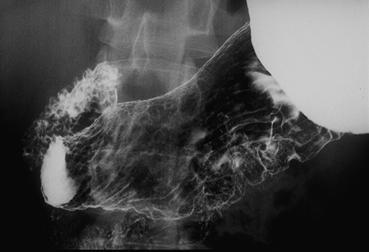

疾病(病理主体)的分类恶性上皮性肿瘤/印戒细胞癌

部位(按器官分)胃(部位)/胃角

检查方法X线

肿瘤的肉眼分类0型(表在型)/IIc型(IIc)

肿瘤最大直径30~34

肿瘤的深度m